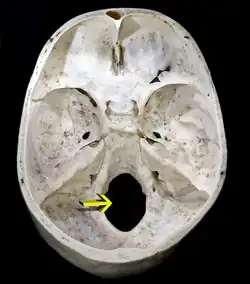

![]() Большое затылочное отверстие в черепе человека, вид сверху | |

Большое затылочное отверстие (лат. Foramen occipitale magnum) — овальное отверстие в затылочной кости черепа, посредством которого черепная полость сообщается с позвоночным каналом. В районе большого затылочного отверстия происходит переход продолговатого мозга в спинной[1]. Правый и левый затылочные мыщелки образуют сочленения с 1-м шейным позвонком. Через это отверстие, самое большое в черепе человека, проходят не только продолговатый мозг, но и корешок добавочного нерва, мозговые оболочки, кортиева мембрана, крыловидные связки и такие элементы кровеносной системы как передняя и задняя спинномозговые артерии и позвоночная артерия[2].

Большое затылочное отверстие ограничено затылочной чешуёй сзади, базилярной частью затылочной кости спереди и соединяющими эти две части затылочной кости затылочными мыщелками (латеральными частями) справа и слева[1][3]. Положение большого затылочного отверстия различается от вида к виду. Так, у человека оно сдвинуто вперёд по сравнению с современными человекообразными обезьянами (в частности, шимпанзе), что соответствует осанке, сформировавшейся в результате прямохождения. Положение большого затылочного отверстия используется палеонтологами для определения того, относить ли тот или иной род ископаемых приматов к гоминидам[4]. В то же время для других двуногих млекопитающих положение большого затылочного отверстия может определяться иными факторами — например, в случае мешотчатых прыгунов и тушканчиковых, увеличившимися в результате эволюции слуховыми буллами[5].